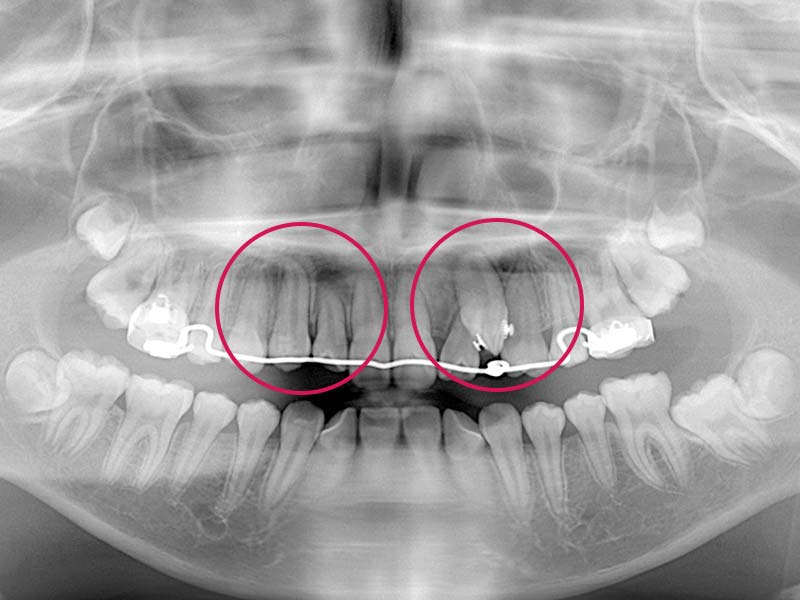

歯ぐきや骨の中に埋まって生えてこない埋伏歯の場合

歯ぐきや骨の中に埋まっている歯を外科的に露出させ、矯正治療で引っ張り出すことがあります。